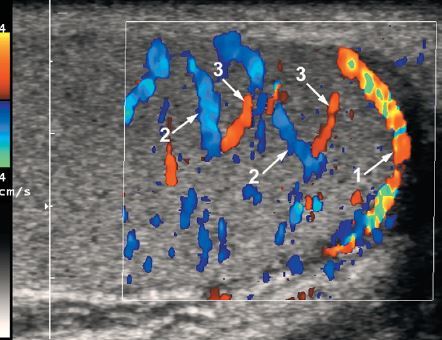

1. capsular artery

2. centripetal artery

3. recurrent artery

4. transmediastinal artery

5. transmediastinal vein